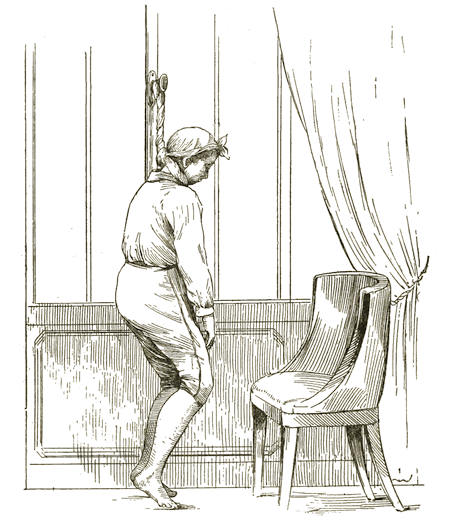

| Medico-Legal Consideration of Death by Mechanical Suffocation. D. S. Lamb, | 705 |